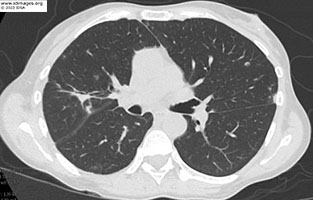

A chest radiography (posterior-anterior and lateral) demonstrated a right upper lobe pneumonia (Figure 1). Computed tomography (CT) of the chest (Figure 2) with contrast demonstrated a mass like consolidative opacity within the right upper lobe containing small foci of gas, concerning for pulmonary abscess. Scattered subcentimeter pulmonary nodules, some are stable but the majority are new.

- Figure 2: Computed tomography scan of chest with contrast.

Patient treated with ceftriaxone IV 2gm every 12 hours for 3 months and sulfamethoxazole-trimethoprim 800-160mg 1.5mg tablets by mouth every 12 hours for plan of at least 12 months of therapy. Repeat CT chest 1 month (Figure 8a) and 6 months (Figure 8b) after start of antimicrobial therapy showed marked improvement in the cavitary consolidation in the right upper lobe. MRI brain after 6 months of treatment with near complete resolution of prior infection (Figure 9b).

- Figure 8A: Computed tomography scan of chest after 1 month of treatment

- Figure 8B: Computed tomography scan of chest after 6 months of treatment